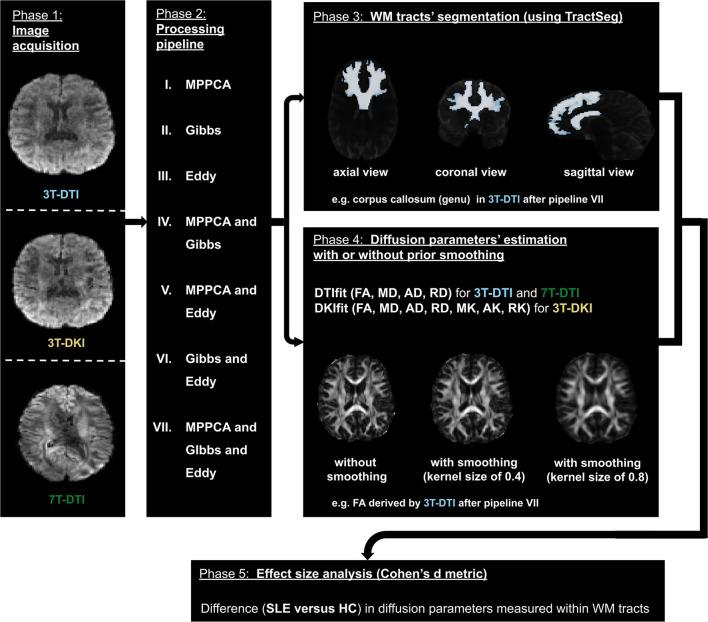

There are many ways to acquire and process diffusion MRI (dMRI) data for group studies, but it is unknown which maximizes the sensitivity to white matter (WM) pathology. Inspired by this question, we analyzed data acquired for diffusion tensor imaging (DTI) and diffusion kurtosis imaging (DKI) at 3T (3T-DTI and 3T-DKI) and DTI at 7T in patients with systemic lupus erythematosus (SLE) and healthy controls (HC). Parameter estimates in 72 WM tracts were obtained using TractSeg. The impact on the sensitivity to WM pathology was evaluated for the diffusion protocol, the magnetic field strength, and the processing pipeline. Sensitivity was quantified in terms of Cohen's for group comparison. Results showed that the choice of diffusion protocol had the largest impact on the effect size. The effect size in fractional anisotropy (FA) across all WM tracts was 0.26 higher when derived by DTI than by DKI and 0.20 higher in 3T compared with 7T. The difference due to the diffusion protocol was larger than the difference due to magnetic field strength for the majority of diffusion parameters. In contrast, the difference between including or excluding different processing steps was near negligible, except for the correction of distortions from eddy currents and motion which had a clearly positive impact. For example, effect sizes increased on average by 0.07 by including motion and eddy correction for FA derived from 3T-DTI. Effect sizes were slightly reduced by the incorporation of denoising and Gibbs-ringing removal (on average by 0.011 and 0.005, respectively). Smoothing prior to diffusion model fitting generally reduced effect sizes. In summary, 3T-DTI in combination with eddy current and motion correction yielded the highest sensitivity to WM pathology in patients with SLE. However, our results also indicated that the 3T-DKI and 7T-DTI protocols used here may be adjusted to increase effect sizes.

在群体研究中,有多种获取和处理扩散磁共振成像(dMRI)数据的方法,但尚不清楚哪种方法能最大程度地提高对白质(WM)病变的敏感性。受此问题启发,我们分析了系统性红斑狼疮(SLE)患者和健康对照(HC)在3T时进行扩散张量成像(DTI)和扩散峰度成像(DKI)(3T-DTI和3T-DKI)以及在7T时进行DTI所采集的数据。使用TractSeg获得了72条WM束的参数估计值。针对扩散协议、磁场强度和处理流程,评估了其对WM病变敏感性的影响。敏感性通过Cohen's 进行量化以用于组间比较。结果表明,扩散协议的选择对效应大小的影响最大。与DKI相比,通过DTI得出的所有WM束的分数各向异性(FA)效应大小高0.26,与7T相比,在3T时高0.20。对于大多数扩散参数而言,扩散协议造成的差异大于磁场强度造成的差异。相比之下,包含或排除不同处理步骤之间的差异几乎可以忽略不计,除了对涡流和运动引起的畸变进行校正有明显的积极影响。例如,对于3T-DTI得出的FA,通过纳入运动和涡流校正,效应大小平均增加了0.07。纳入去噪和吉布斯环去除后,效应大小略有降低(分别平均降低0.011和0.005)。在扩散模型拟合之前进行平滑处理通常会降低效应大小。总之,3T-DTI结合涡流和运动校正对SLE患者的WM病变具有最高的敏感性。然而,我们的结果还表明,此处使用的3T-DKI和7T-DTI协议可能需要调整以增加效应大小。